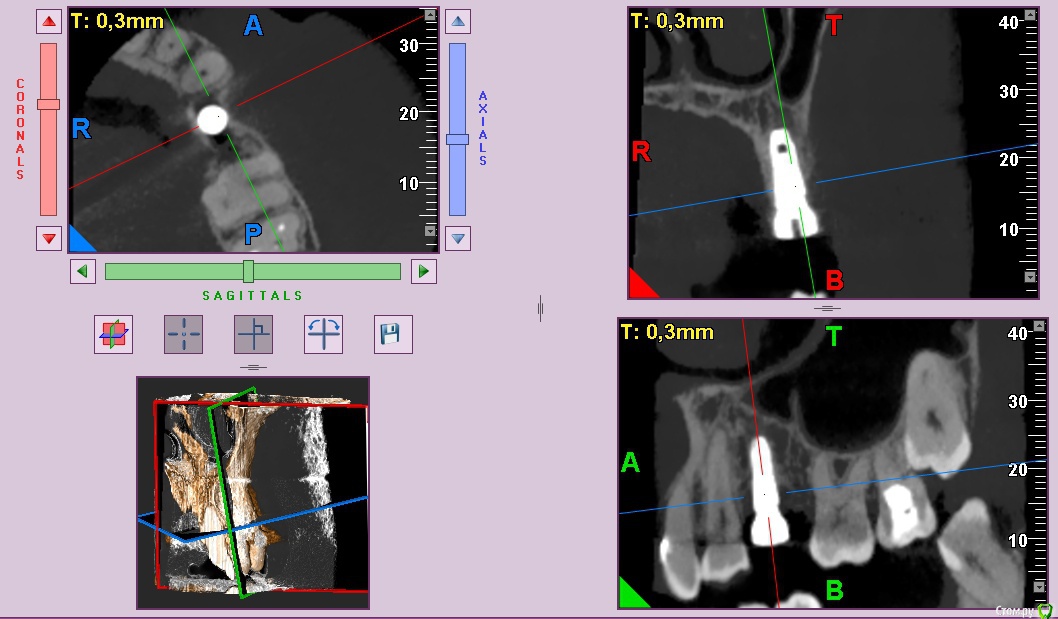

колесников Опубликовано 25 февраля, 2017 Поделиться Опубликовано 25 февраля, 2017 Здравствуйте коллеги! Представляю вашему вниманию этот клинический случай.В ноябре 2016 обратилась пациентка с жалобами на выпадение ортопедической конструкции в обл 24. Объективно: корни 24 не состоятельны. ,на десневом крае в проекции 24 свищевой ход с гнойным отделяемым.На КТ резорбция вестибулярной компактной пластинки и деструкция костной ткани в области щёчного корня.Приняв во внимание крайне негативное отношение пациентки к каким бы то ни было хирургическим вмешательствам и высоким эстетическим требованиям,было решено пойти на немедленную имплантацию .Снимки в день вмешательства,через 7,14 дней и 3мес.Имплант Astra tech profile 4.5х11мм. Сст с бугра вестибулярно. Вместо графта губки Коллапола (не вспомню причину,либо не было в наличии,либо отказ пациента). 15 Ссылка на комментарий

колесников Опубликовано 12 июня, 2017 Автор Поделиться Опубликовано 12 июня, 2017 Контрольное кт спустя 3 мес. Откуда-то наросло 2мм у шейки. Ссылка на комментарий

Doctor Vlad Опубликовано 13 июня, 2017 Поделиться Опубликовано 13 июня, 2017 Откуда-то наросло 2мм у шейки. да видимо графт был, причем не коллапон коллагеновый а костная стружка, даже по первым снимкам после операции там чтото рыхлое торчит. Ссылка на комментарий